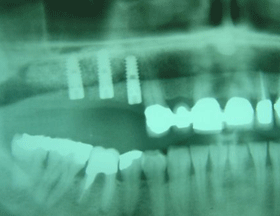

This X-ray shows 9 CAMLOG dental implants (upper jaw) & 4 NOBEL BIOCARE – BRANEMARK dental implants (lower jaw) placed, which required another 6 months healing period before final restorations can be safely loaded onto implants.

This X-ray shows the final result with the full arch 12 unit dental bridge secured onto 9 Camlog implants (upper jaw) and 4 new dental bridges secured onto 8 Branemark (4 new and 4 previously placed) implants.

Successful sinus lifts and cortical bone transplant, which were required to build up the upper jaw bone, are also visible on this X-ray. Safe placement of implants would not have been possible without those bone augmentation procedures.